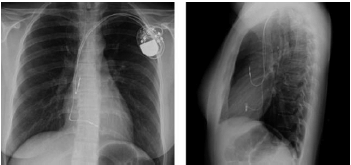

Uma paciente com história de síncope e períodos de bloqueio atrioventricular total foi submetida a implante de marcapasso definitivo.

De acordo com sua radiografia de tórax, o tipo de dispositivo mais provável é o